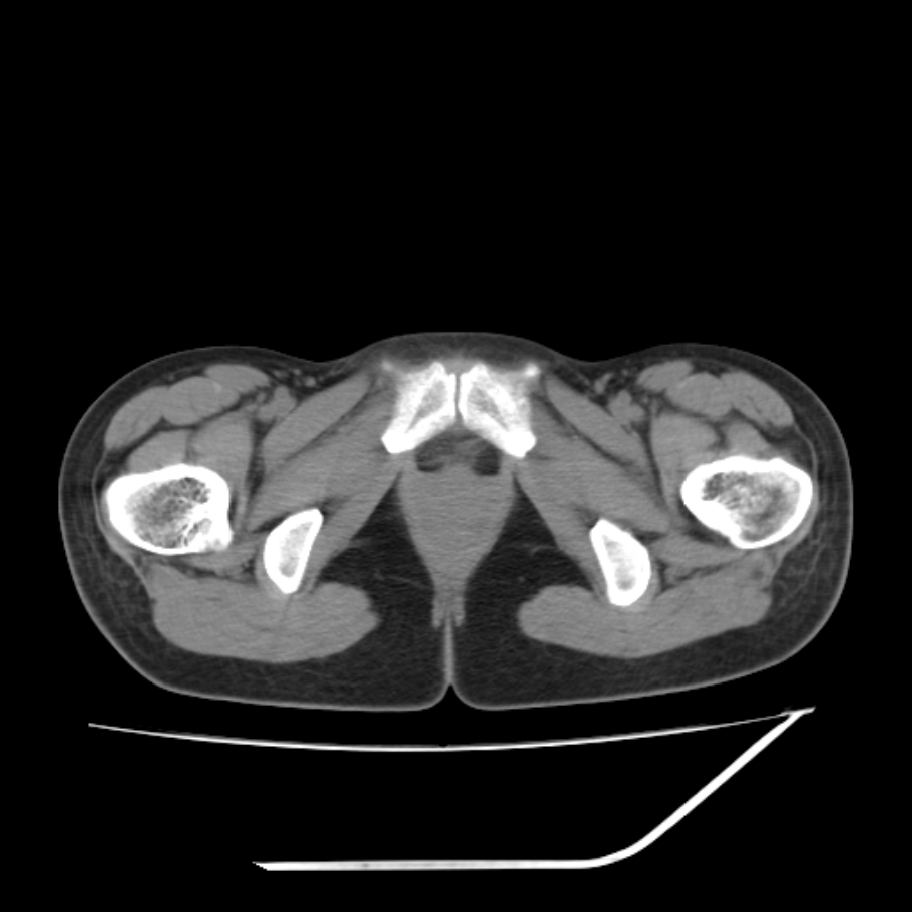

女,25岁。偶尔有右下腹不适感,余无明显异常。(结婚半年),囊壁较厚,是卵巢囊肿吗?

右侧卵巢区椭圆形囊性肿物,内壁光滑 无分隔。直肠子宫间隙内有少量积液征象。结合临床考虑卵巢巧克力囊肿,还要问问有没有痛经,本例ct怎么没有灌肠?要是灌肠或前一前口服造影剂,起码可以和肠管区别开

b超示:囊实性占位,畸胎瘤?临床有痛经。

考虑右侧卵巢囊性占位性病变(巧克力囊肿?),盆腔积液有不排除宫外孕可能,请结合临床和b超。

右侧卵巢囊伴盆腔少量积液。